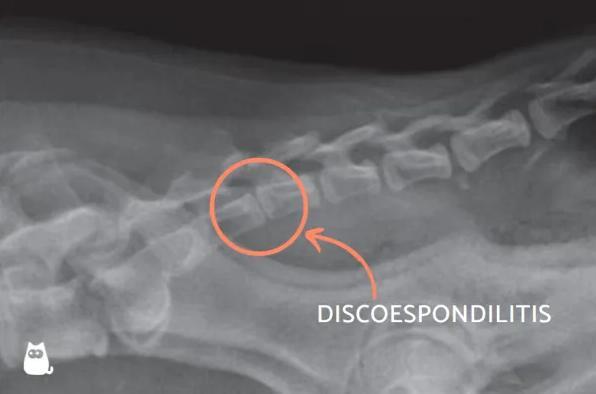

Infecção da coluna vertebral

Se você já mencionou a frase "meu cachorro grita de dor do nada", isso pode ser um sinal de uma infecção da coluna vertebral. A infecção nas vértebras é conhecida como discoespondilite, pois é um processo infeccioso que afeta os discos intervertebrais, resultando em deformação óssea, além de irritação e inflamação que podem comprimir a medula espinhal, causando forte dor e até alterações na marcha ou perda de mobilidade.

Os discos intervertebrais funcionam como amortecedores entre as vértebras, evitando o atrito entre elas. Eles se infectam quando são atingidos por micro-organismos, geralmente provenientes da cavidade oral, do sistema respiratório, válvulas cardíacas, pele ou sistema urinário. Para mais informações, consulte o artigo "Doenças da coluna vertebral em cachorros".